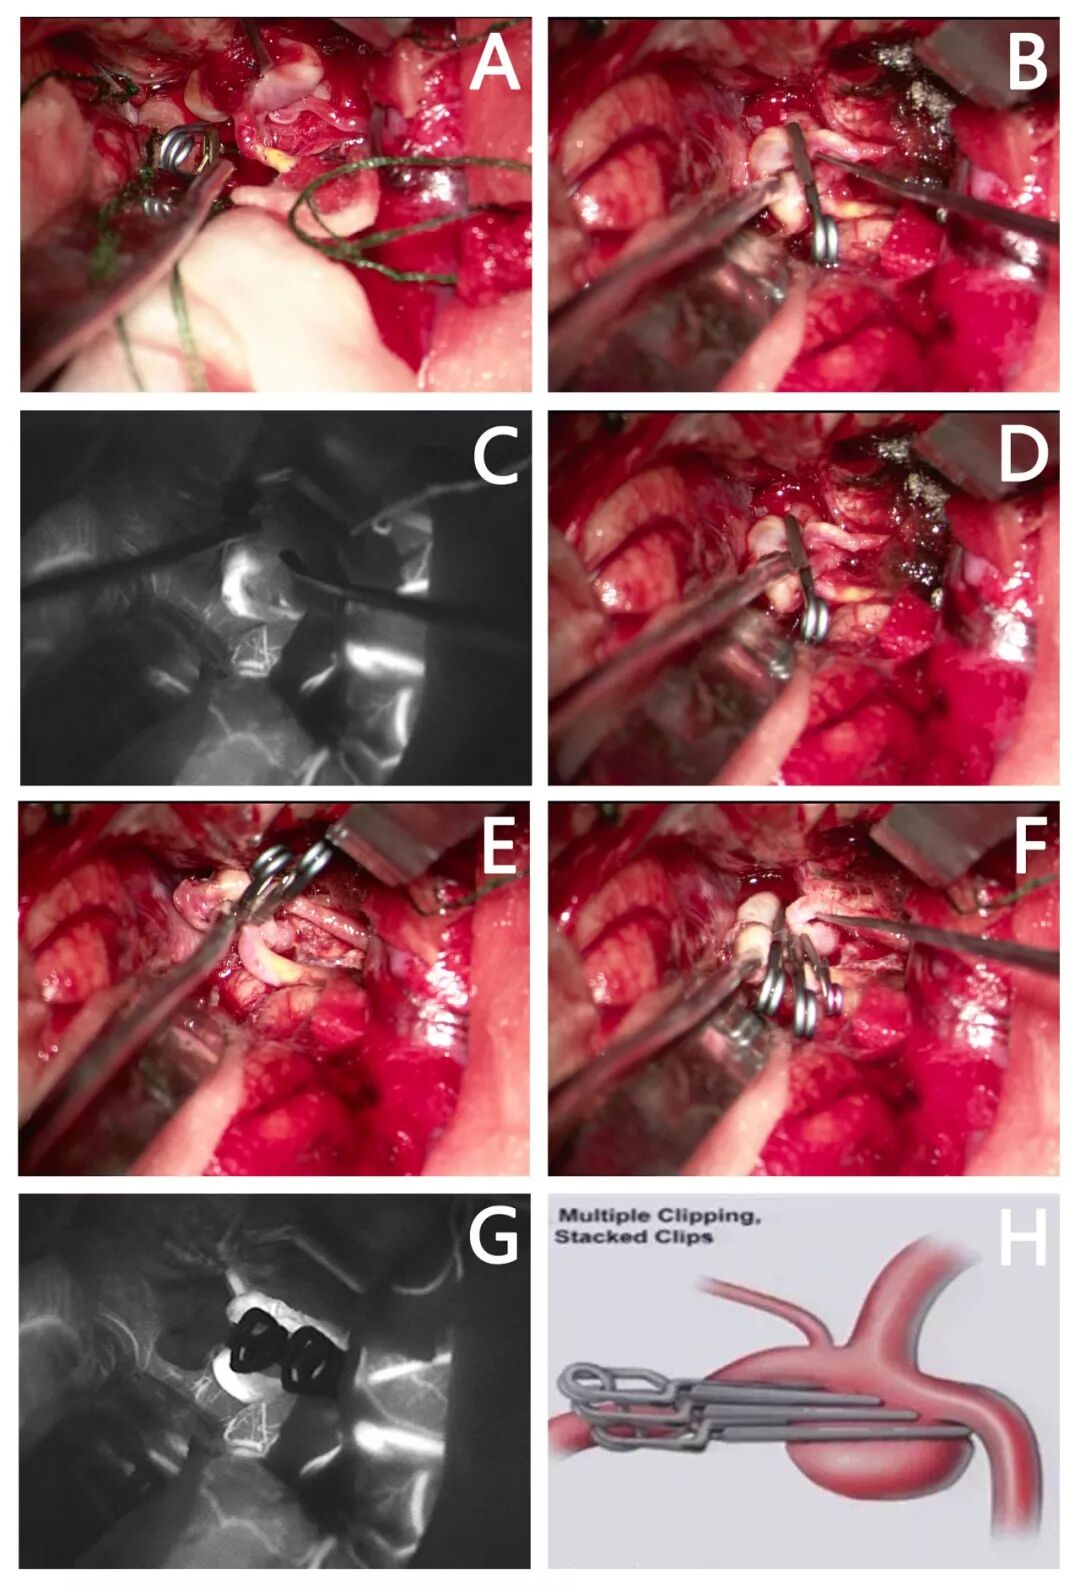

取左侧翼点手术入路,显微镜下沿左侧外侧裂向深部探查,于M1末端分叉部探查见动脉瘤,大小约7*8mm,瘤颈宽约6mm,朝向外上方,予周围粘连分离并充分暴露动脉瘤颈后,予临时动脉瘤夹夹闭大脑中动脉M1段(图1A),动脉瘤颈予754动脉瘤夹一枚夹闭后(图1B),荧光造影确认瘤腔内无荧光显影,但是探查见瘤颈仍有部分残留(图1C,D),遂予720迷你动脉瘤夹一枚完整夹闭残余瘤颈(图1E),再次荧光造影确认动脉瘤夹闭完全,载瘤血管及分支血管荧光显影良好(图1F)。

图2. 患者手术中动脉瘤夹闭及分支血管保留情况。(A)探查并分离动脉瘤周围粘连后充分暴露动脉瘤颈,予临时动脉瘤夹夹闭大脑中动脉M1段;(B)尝试予754动脉瘤夹一枚完整夹闭动脉瘤;(C)荧光造影确认瘤腔内无荧光显影,但是探查见瘤颈仍有部分残留;(D)显微镜下见动脉瘤残留瘤颈,尝试予720迷你动脉瘤夹组合夹闭;(E)予组合夹闭后,显微镜下探查见动脉瘤夹闭完全,载瘤血管及各分支保留完好;(F)荧光造影确认动脉瘤夹闭完全,瘤腔内无荧光显影,载瘤血管及各分支显影良好;(G)组合夹闭技术示意图。

取右侧翼点手术入路,显微镜下沿右侧外侧裂向深部探查,于M1末端分叉部探查见动脉瘤,大小约10*8mm,瘤颈宽约7mm,朝向外下方,予周围粘连分离并充分暴露动脉瘤颈后,予临时动脉瘤夹夹闭大脑中动脉M1段(图1A),动脉瘤颈予750动脉瘤夹一枚夹闭后(图1B),荧光造影确认瘤腔内无荧光显影,但是探查见一分支血管无荧光显影(图1C),遂予调整动脉瘤夹位置和角度,夹子稍外移,此时瘤颈部分残留(图1D),再予740,720动脉瘤夹两枚完整夹闭动脉瘤残余瘤颈(图1E,F),探查见瘤颈无残留,载瘤血管及分支血管完整(图1F),再次荧光造影确认动脉瘤夹闭完全,载瘤血管及两分支血管显影良好(图1G)。

图5. 患者手术中动脉瘤夹闭及分支血管保留情况。(A)探查并分离动脉瘤周围粘连后充分暴露动脉瘤颈,予临时动脉瘤夹夹闭大脑中动脉M1段;(B)尝试予750动脉瘤夹一枚完整夹闭动脉瘤;(C)荧光造影确认瘤腔内无荧光显影,但是探查见一分支血管无荧光显影;(D)显微镜下调整动脉瘤夹位置和角度,夹子稍外移,此时瘤颈部分残留;(E)再予740动脉瘤夹一枚夹闭动脉瘤残余瘤颈,瘤颈仍少量残留;(F)最后予720迷你夹一枚完整夹闭少量残留瘤颈;(G)荧光造影确认动脉瘤夹闭完全,瘤腔内无荧光显影,载瘤血管及各分支显影良好;(H)组合夹闭技术示意图。